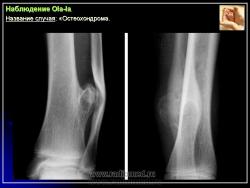

Наблюдения коллег.